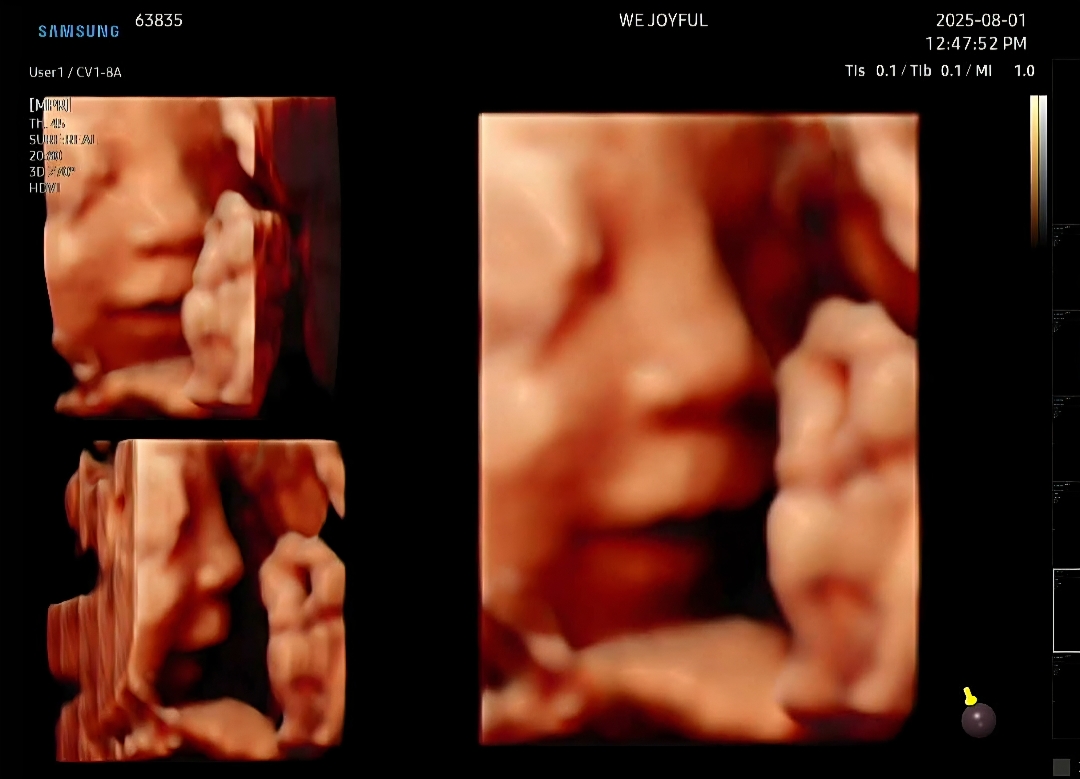

헤~하고 웃고있는 입체초음파 보고왔어요

귀여운 울애기 25주 0일차 입체초음파 하고왔어요ㅎㅎㅎ계속 손 올리고 있어서 얼굴 찍는데 1시간 정도 걸렸어요 ㅋㅋ 중간에 물마시고 초콜렛 먹었지만 끝까지 손은 안내려주던 울애기 기분은 좋은지 헤~하고 웃은 모습이 찍혀서 ㅎㅎ덩달아 넘 기분좋았어요 입체초음파만 봐도 이렇게 귀여운데 태어나고 나면 얼마나 도치맘이 될지..ㅎㅎ벌써 걱정되네요 ㅋㅋ